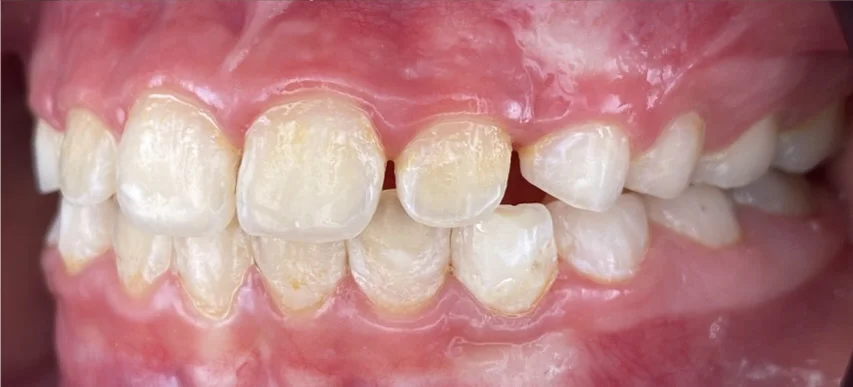

Търсейки детски ортодонт, пациентът дойде с основни оплаквания – “Долните зъби са пред горните” Кръстосаната захапка във фронта, затруднение при отхапване, нарушена естетика.

Кръстосана захапка във фронталния участък

Компресия на челюстите

Струпване и липса на място за пробива на постоянните зъби

- Интраорални и екстраорални снимки